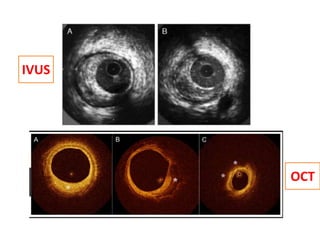

IVUS

OCT